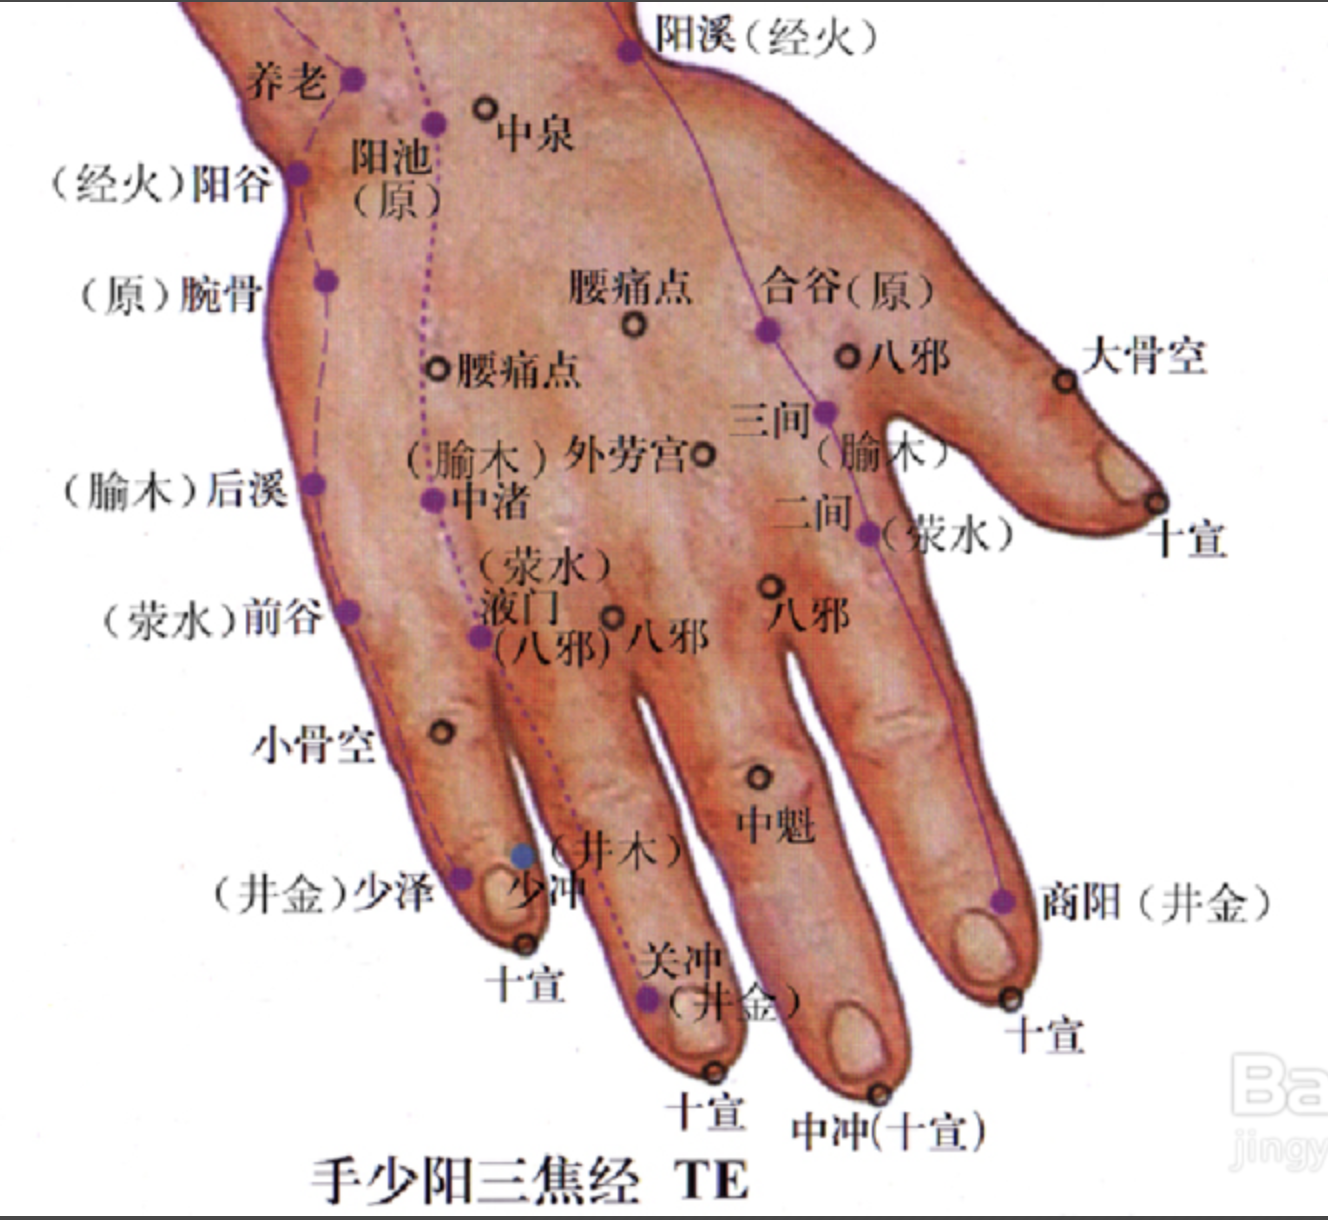

腰痛点

【定位】 在手背侧,当第 2、第 3掌骨及第 4、第 5 掌骨之间,当腕横纹与掌指关节中点处,一侧 2 穴,左右共 4 穴。

【主治】 急性腰扭伤。

【刺灸法】 由两侧项掌中斜刺 0.5 ~ 0.8 寸;可灸。

外劳宫

【定位】 在手背侧,当第 2、第 3掌骨间,指掌关节后约 0.5 寸处。

【主治】 落枕,手臂痛,胃痛。

【刺灸法】 直刺或斜刺 0.5 ~ 0.8 寸。

八邪

【定位】 在手背侧,微握拳,第 1 至第 5 指间,指蹼缘后方赤白肉际处,左右共 8 穴。

【主治】 手背肿痛,手指麻木,烦热,目痛,毒蛇咬伤。

【刺灸法】 斜刺 0.5 ~ 0.8 寸,或点刺出血。

四缝

【定位】 在第 2 至第 5 指掌侧,近端指关节的中央,一手 4 穴,左右共 8 穴(图 10-36)。

【主治】 小儿疳积,百日咳。

【刺灸法】 点刺出血或挤出少许黄色透明黏液。

十宣

【定位】 在手十指尖端,距指甲游离缘 0.1 寸(指寸),左右共 10 穴(图10-36)。

【主治】 昏迷,癫痫,高热、咽喉肿痛。

【刺灸法】 浅刺 0.1 ~ 0.2 寸,或点刺出血。